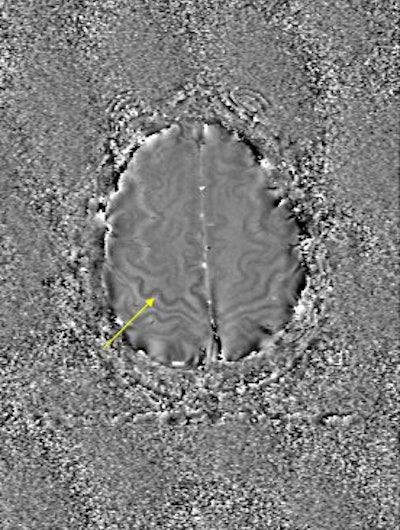

He also presented a trauma case comparing 2D conventional gradient-echo imaging (TE = 20 msec) and SWI. The patient had an accident and suffered subsequent cognitive impairment.

"This is where SWI lets you start seeing very small, almost pixel-like effects, probably microhemorrhages where there may be damage," he said. "Conventional gradient-echo imaging didn’t show any effects, but on the SWI you could see evidence of microhemorrhages and edema (see below). In most cases, you will see something with SWI that you won't see with conventional imaging. It could have significant impact in trauma imaging because you'd like to know what's wrong with them, and whether they are going to get better."

| Diffuse axonal injury in trauma. GRE image above; SWI image below. Data was collected on a 1.5-tesla scanner (Vision, Siemens Medical Solutions) with a TE = 40 msec and a resolution of 0.5 mm x 1.0 mm by 2.0 mm. Images courtesy of Dr. Karen Tong, Loma Linda University. |